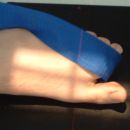

Lagerung

Patient sitzt auf dem Tisch, Fuß plantar aufgestellt (evtl. auf einem Stuhl), bei verkrümmten Zehen mit Zellstoff unterpolstern.

Lagerung

Pat. sitzt auf dem Tisch, Fuß mit der medialen Seite aufliegend, die anderen Zehen mit Band zurückziehen.

1. Möglichkeit: Patient liegt auf dem Rücken, das Sprunggelenk wird zum Kopf angezogen. Mit einem Band werden die Zehen in Richtung Knie gezogen.

2. Möglichkeit: Patient liegt auf dem Bauch, der Fuß wird so aufgestellt, dass die Plantarseite der distalen Zehenglieder an die Kassette gelehnt wird. Das Sprunggelenk steht im rechten Winkel, die Zehen sind in Dorsalflexion.